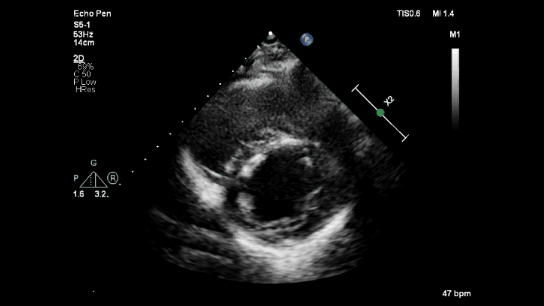

Echocardiography

Echocardiography in right ventricular myocardial infarction (RVMI) can resemble McConnell's sign.

Parasternal short axis reveals RV dilatation with preserved LV contraction.

RV dilatation with RV dysfunction with preserved apical contractility resembles McConnell's sign.